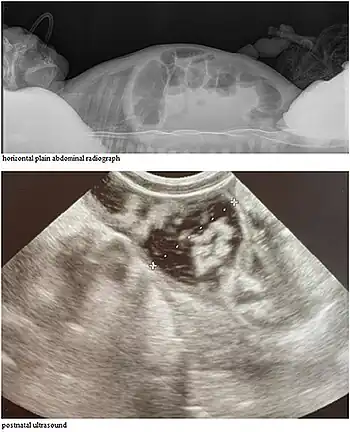

Abdominal ultrasound exam shows significantly distended intestinal loops of newborn

CCD may be detectable on prenatal ultrasound.[4][5]

CCD causes persistent secretory diarrhea. In a fetus, it leads to polyhydramnios and premature birth. Immediately after birth, it leads to dehydration, hypoelectrolytemia, hyperbilirubinemia, abdominal distention, and failure to thrive.[3]